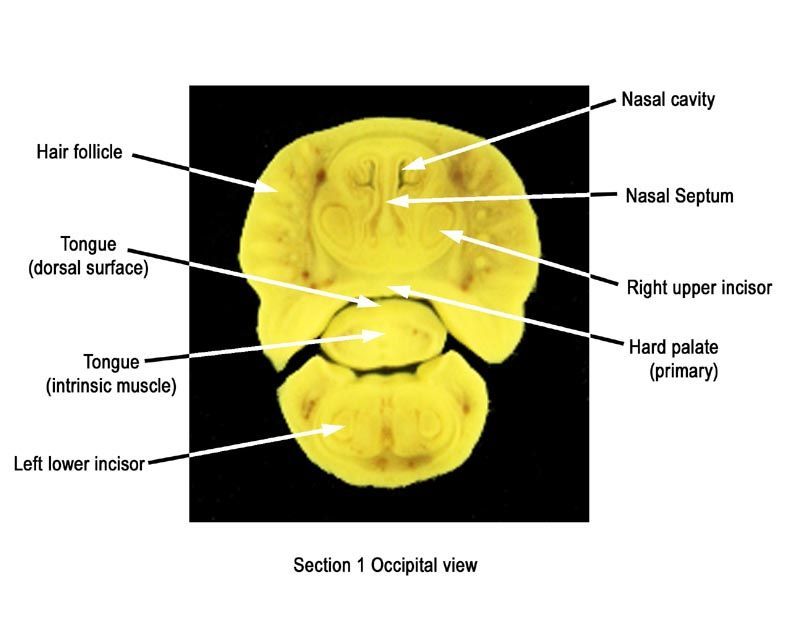

The images below show the normal appearance of Bouin's fluid fixed head sections in specimens at Day 21 of gestation (day mating observed = Day 0).

Learning objective: Compare the diagrams with your own specimens and identify all of the structures that have been labelled.

Labelled Images